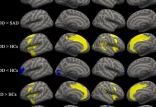

نتایج یک مطالعه جدید نشان میدهد که مدیتیشن میتواند فعالیت مغز انسان را از نو شکل دهد.

[ادامه]